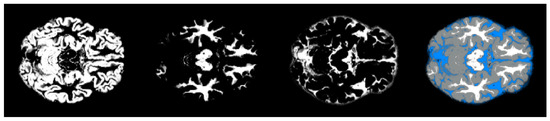

- We have introduced the notion of significant pixels, i.e., the pixels of the MRI images where the white (resp. gray) matter decays in the considered two-year time span, significantly differ between and subjects. The number of significant pixels, in the brain slices where the phenomenon mostly appeared, according to the different values obtained after performing a permutation test on all the pixels of the images, i.e., , , and , was about 4%, 2%, and 1.5% of the totality of the white matter and slightly more, i.e., 6%, 4%, and 2.5%, of the totality of the gray matter. Such a small number of significant pixels is sufficient to discriminate between and , as reported in Table 2 and Table 3, using the K-means clustering technique. Not surprisingly, when considering the white matter, all the and subjects were correctly clustered, i.e., the white matter decay of subjects significantly differed from that of ones. On the other hand, when considering gray matter, the subjects were correctly classified, while 6 of the 40 subjects were assigned to the class, with a percentage of error of 15%. This can be ascribed to the fact that Alzheimer’s disease strongly impacts on the white matter first, and later leads to the decay of the gray matter.We also underline that, according to the wide and consolidated literature, the most involved areas of the brain affected by Alzheimer’s decay are the medial portion of the temporal lobe, where the hippocampus, amygdala, entoryl cortex, and parahippocampal cortex reside. These areas are located inside the selected slice intervals where most of the significant pixels were detected. As an example, Figure 7 shows the significant pixels of slice 58, where a peak in the white and gray matter occurred, with the involved brain areas highlighted.

- Moving to the -to- predictive capability of the K-means model restricted to significant pixels, again we found different percentages according to the considered white or gray matter in the considered two-year time span. As expected, analyzing the white matter a high percentage of , namely, (Table 2), showed an pattern-like decay, similar to what was detected in [16,17,18] on the same dataset. So, our result, with a time span of two years, was slightly below the results presented in [20], where after one year only 8 of 37 patients with converted to (22%), verifying the reduction in the regional glucose metabolic rate, a truthful signal of early-onset .This high percentage of pattern in could be attributed to the similarly located decay of white matter in the two classes of subjects, as reported in [43]. This study involved 23 , 15 , and 15 subjects that underwent diffusion tensor magnetic resonance imaging (DTI), an advanced MRI technique extremely sensitive to white matter alterations. The authors found that patients with had an increase in mean diffusivity in the limbic, interhemispheric, cortico-cortical, and corticospinal tracts and, similarly, patients with showed an increase in axial diffusivity only in tracts projecting to the frontal cortex and splenium of the corpus callosum.On the other hand, time passing caused a milder effect on the gray matter of subjects, whose analysis revealed only 29% of -to- cases (see Table 3),, in accordance with the more optimistic studies in the work of [8], obtained through using machine learning techniques on fMRI images.Table 2 and Table 3 report the obtained statistics on the classification performance of subjects, together with the related indexes. In Figure 6, the distributions of subjects’ distances within the clusters show smaller distances between the subjects and the related centroids when white matter is considered with respect to gray matter. This implies that the classification using white matter produces tighter clusters and, consequently, a stronger accuracy than gray matter. All the clusters show some borderline subjects that produce small local maxima while moving away from the centroids. However, the computation of the Dunn indexes showed the high reliability of the obtained clustering. Again, we underline that the small diameter of the cluster may also be due to the smaller variability in the age range of the subjects. However, this does not constitute an issue in the final results of the research.